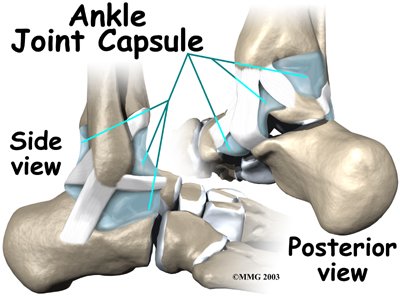

The ligaments that surround the ankle joint help form part of the . A joint capsule is a watertight sac that forms around all joints. It is made up of the ligaments around the joint and the soft tissues between the ligaments that fill in the gaps and form the sac.